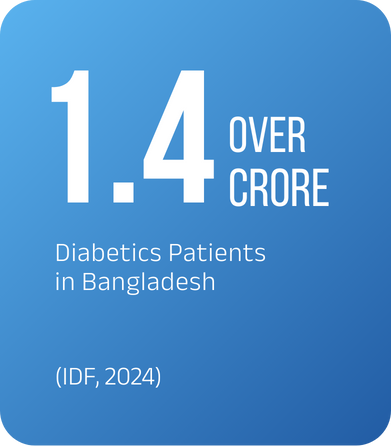

Fact :

- Over 1.4 Crore diabetics in Bangladesh (IDF, 2024)

Diabetic Retinopathy (DR) is a silent epidemic in Bangladesh. With over 14 million people living with diabetes, studies show that 1 in 3 is at risk of developing DR. If left undiagnosed, this condition can cause irreversible blindness.